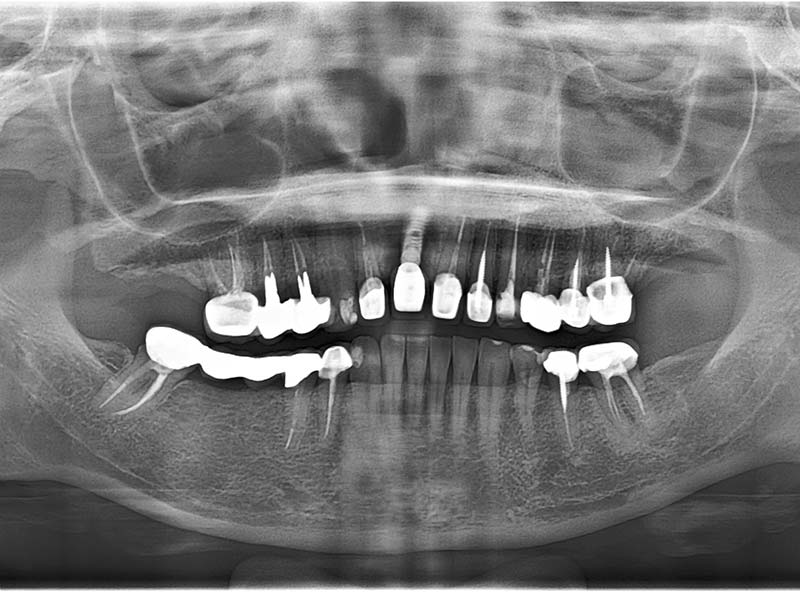

治療前

治療後